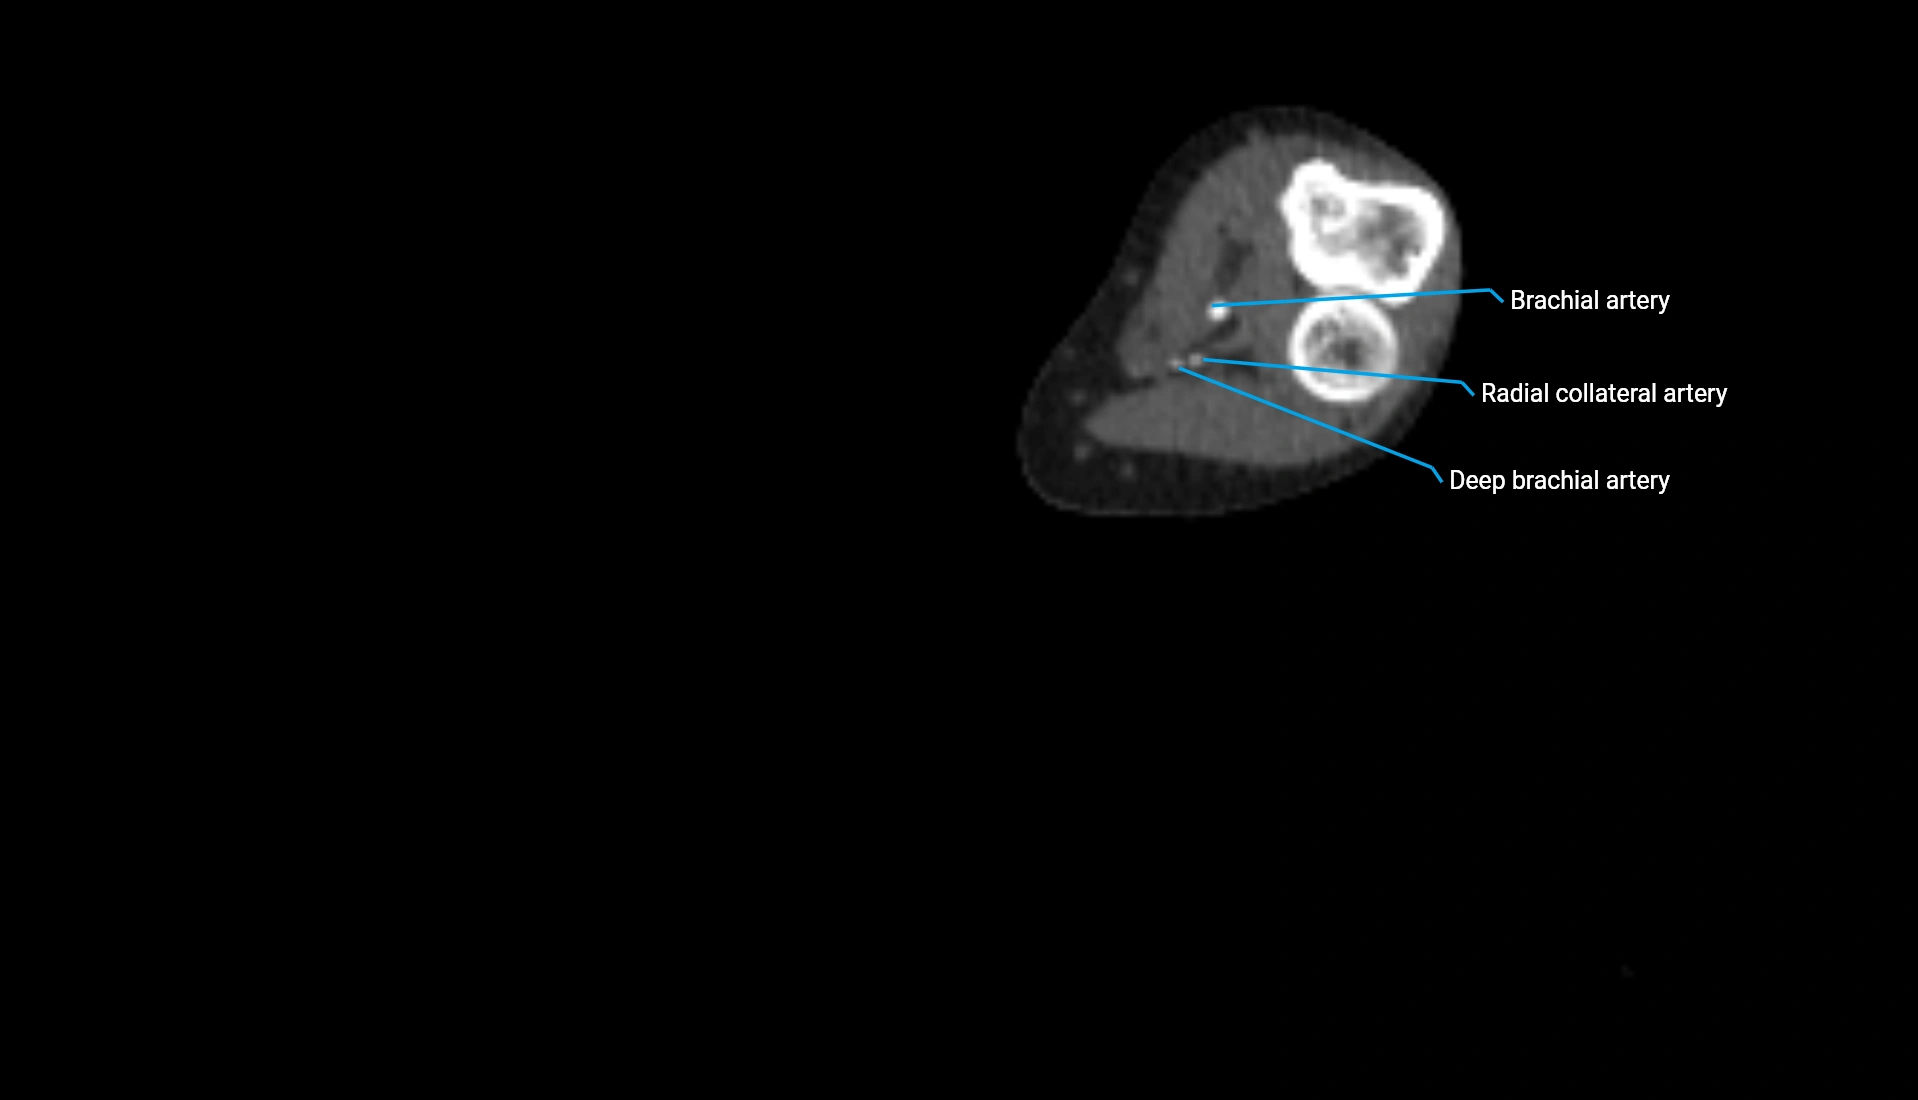

CT Appearance

Non-Contrast CT:

• Cortex: High-density, sharply defined

• Subchondral bone: Dense cancellous matrix

• Articular surface: Smooth concave contour articulating with the capitellum

• Excellent for evaluating bone integrity, alignment, and subtle fractures